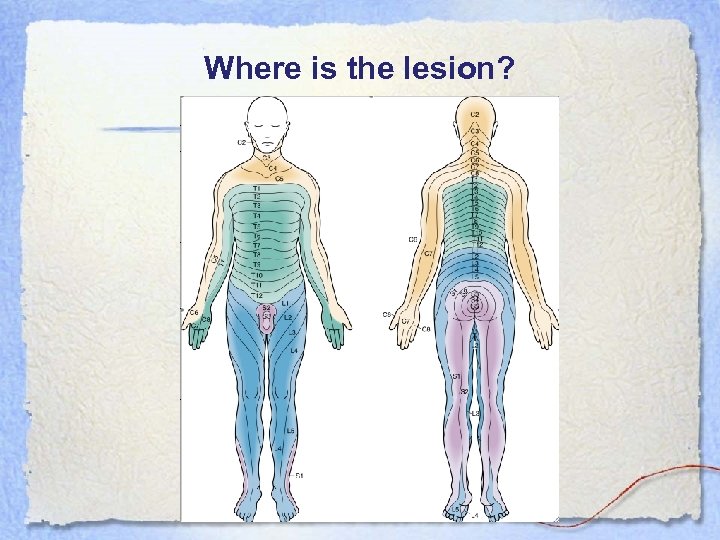

Where is the lesion?

Where is the lesion?